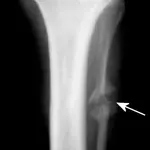

Figure 5A. An obvious fracture is not seen on this lateral radiographic view of the radius and ulna.

Figure 5B. A nondisplaced hairline fracture of the distal radius (arrow) that involves the medial cortex of the distal radius is easily seen, demonstrating the need for multiple radiographic views.